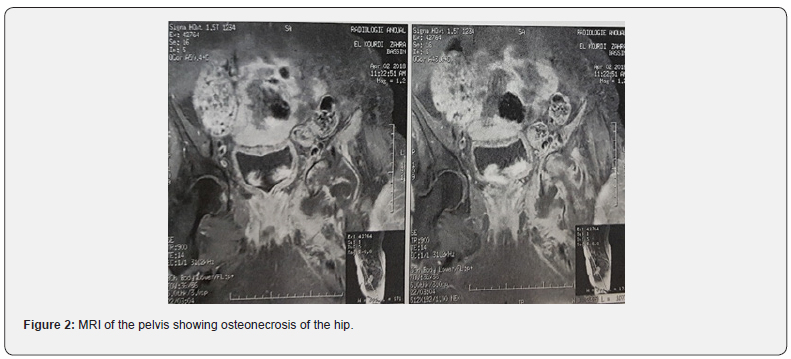

A radiograph of the pelvis showed an acetabular osteolysis with protrusion, destruction of the left femoral head and pathological central dislocation of the hip (Figure 1a). Computed Tomography (CT) revealed irregular Osteolytic process of the acetabulum with an ill-defined border and femoral head destruction, with intra-articular bone fragments (Figure 1b). Magnetic Resonance Imaging (MRI) of the pelvis revealed a remodeling of the left hip in T1 hyposignal and hypersignal in T2 and STIR, moderately enhanced by the contrast product and severe destruction of the femoral head, suggestive of osteonecrosis of the hip (Figure 2). The bone scan revealed increased uptake in the left acetabulum and femoral head, but there were no other suspicious areas of increased uptake to suggest metastases (Figure 3). To eliminate the diagnosis of bone metastasis or Septic arthritis of the hip joint, a CT‑guided biopsy was arranged showing Chronic inflammatory remodeling without evidence of malignancy, with signs related to bone avascular necrosis. Via a standard posterolateral approach, the patient underwent a total hip arthroplasty, by a cemented femoral and acetabular component. In order to fill the bone loss, we used a cemented reconstruction with the addition of a Kerboull reinforcement cross. With use of bone graft from the femoral head (Figure 4). Cultures obtained at the time of surgery were negative. Pathological examination confirmed osteonecrosis. She received twenty days of thrombo-embolic prophylaxis with low molecular weight heparin with Post-operative rehabilitation and fully weight-bearing mobilization immediately after the operation. At 12 months follow-up she had no pain over the left hip and could walk without sticks, the Postel Merle d’Aubigné (PMA) score was 17.